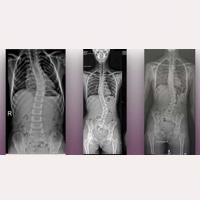

Septembre : mois de sensibilisation au syndrome d’Arnold-ChiariNOUS CLARIFIONS LES DOUTESsur le syndrome de type I et son approche par le Filum System® Lire plus » 28 septembre, 2025